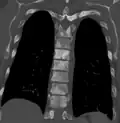

Sclerosis of the bones of the thoracic spine due to prostate cancer metastases (CT image) -

Sclerosis of the bones of the thoracic spine due to prostate cancer metastases (CT image)